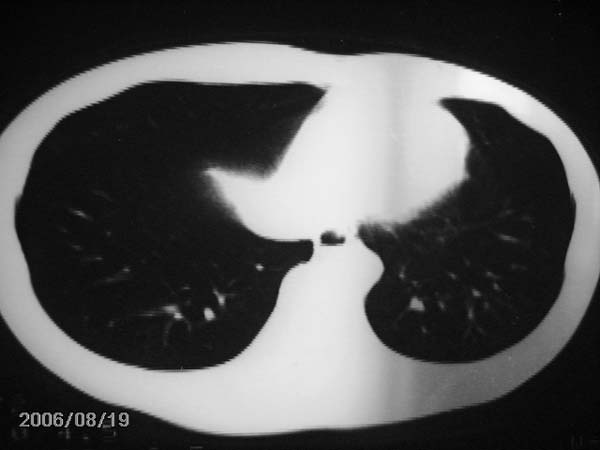

男,13岁,发烧半月,干咳无痰,正规使用抗生素半月,现在仍是午后低烧!!!未做痰检

右肺结核,右肺中叶不张

右中肺呈大片状密度欠均匀影,内见含气支气管.

结合病史,考虑:右中肺大叶性肺炎(吸收期).

右肺中叶大片状密度增高影,内密度不均匀,右肺门处增大,应该是淋巴结肿大,结合临床首先考虑原发性肺结合可能性大,不排除合并感染可能,建议治疗后复查.

灶内密度不均,似乎有囊状,条状影,考虑右中叶综合症; 从照片中看不出有无钙化灶,若明显则考虑结核性。

肺结核中叶综合征

考虑中叶综合征(右肺门肿大淋巴结伴中叶阻塞性炎症)